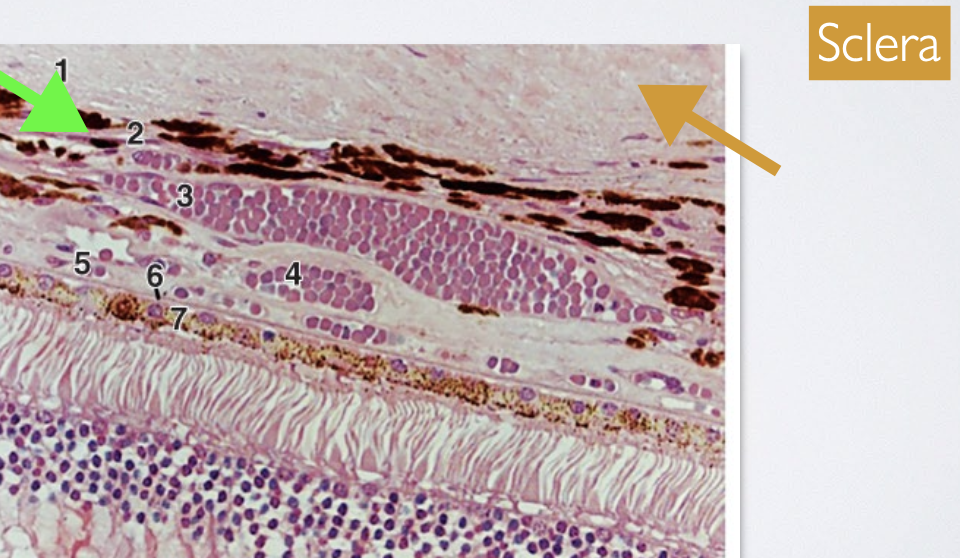

List the layer of the Choroid from (external to internal)

→ divided based on vessel size in each layer

Suprachoroid (suprachoroidal space)

Haller’s layer of large vessels

Sattler’s layer of medium vessels pigmented CT stromal matrix

Choriocapillaris

Bruch’s membrane

Where do the various layers of vessels of the choroid reside within?

pigmented CT stromal matrix

What is the Suprachoroid layer?

→ “potential space (2)” b/w the sclera (lies internal to the lamina fusca of the sclera) and choroid, where “could” travel through

it’s a thin pigmented CT layer

What is the Haller’s layer?

has large blood vessels + closest to the sclera (3)

What is the Sattler’s layer?

has medium blood vessels + lies under the Haller’s layer, closer to the choriocapillaris (4)

What is the Choriocapillaris layer?

→ functional capillary bed of the choroid that supplies nutrients & O2 to the avascular outer retina (photoreceptors and RPE) (5)

has the largest capillaries in the body

these capillaries are fenestrated ONLY along the surface facing the retina (Bruch’s membrane), not on the side facing deeper choroidal layers

fenestrations allow for the rapid passage of nutrients and O2

What is the Bruch’s membrane?

→ a thin compound BM complex enveloping layers of collagen & elastin b/w the BM of the choriocapillaris and that of the RPE (6)